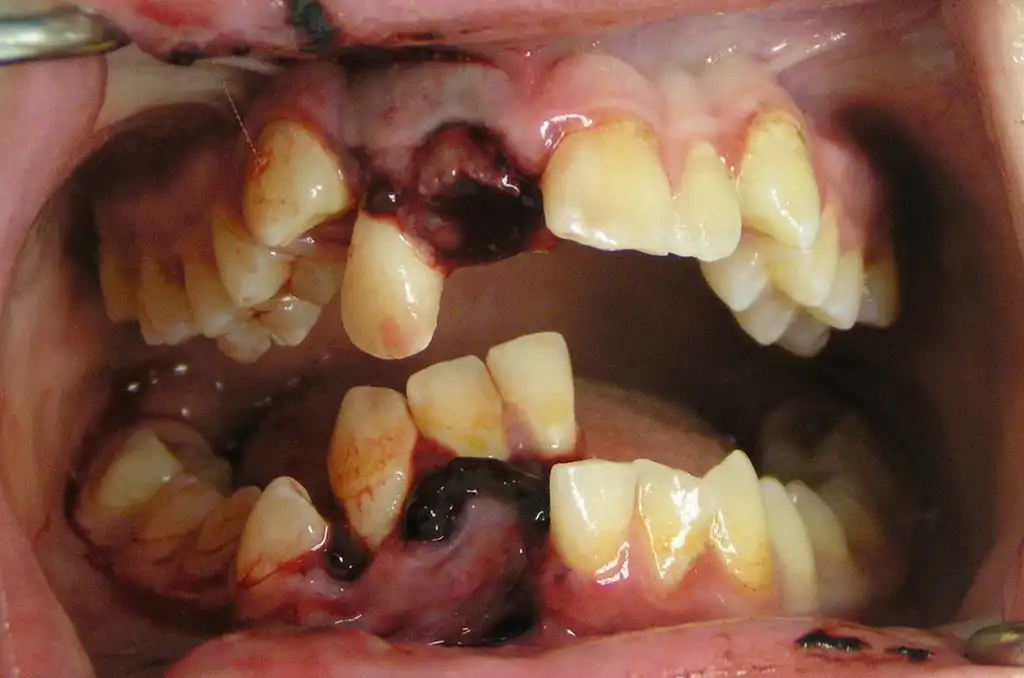

Жестокие фото